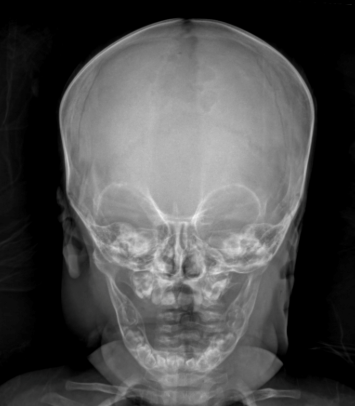

Hannah was only the second child to undergo this new cranial surgery to correct her craniosynostosis. Parts of Hannah's skull fused too early, causing her head to become misshapen. The condition can cause an abnormal head shape, developmental delays, and increased brain pressure.

"Craniofacial surgery is still relatively new as a discipline. Historically, it has meant taking the skull apart and putting it back together. As you can imagine, that's a pretty big deal for a little baby," Nguyen explained. "We're seeing more and more now, children presenting so early, and that's actually a testament to pediatricians and other folks who are referring to us because they know something's not quite right. Because the kids are coming early, it offers us an opportunity to intervene earlier, but we have to devise a way to make it safe while still reaching the same goals and minimizing the amount of risk."

Nguyen said that for children under 6 months old, there is the ability to perform a minimally invasive surgery as opposed to an operation in which doctors take the skull apart. The traditional surgery, called an endoscopic strip craniectomy, requires a child to wear a helmet for roughly 12 months after the procedure to help mold their skull.

"That just means removing that part of the bone that's fused and then letting the brain do the rest," Nguyen said. "It works sometimes, and the reason I say sometimes is because with the unpredictability of what your head shape is going to be because you are just releasing the suture and allowing the brain to push out. It also requires a molding helmet to kind of help shape and steer where that skull is going to go, what it's going to look like. But that process can take up to 12 months or more, and that means wearing a helmet."